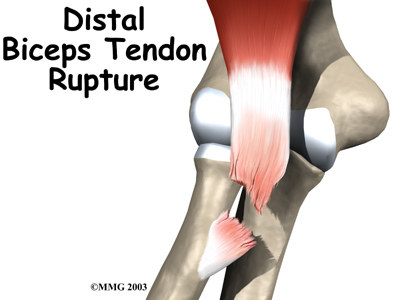

A distal biceps rupture occurs when the tendon attaching the biceps muscle to the elbow is torn from the bone. This injury occurs mainly in middle-aged men during heavy work or lifting. A distal biceps rupture is rare compared to ruptures where the top of the biceps connects at the shoulder. Distal biceps ruptures make up only three percent of all biceps tendon ruptures.

The biceps muscle goes from the shoulder to the elbow on the front of the upper arm. Tendons attach muscles to bone. Two separate tendons connect the upper part of the biceps muscle to the shoulder. One tendon connects the lower end of the biceps to the elbow.

The lower biceps tendon is called the distal biceps tendon. The word distal means that the tendon is further down the arm. The upper two tendons of the biceps are called the proximal biceps tendons, because they are closer to the top of the arm.

The attaches to a small bump on the radius bone of the forearm. This small bony bump is called the radial tuberosity. The radius is the smaller of the two bones between the elbow and the wrist that make up the forearm. The radius goes from the outside edge of the elbow to the thumb side of the wrist. It parallels the larger bone of the forearm, the ulna. The ulna goes from the inside edge of the elbow to the wrist.

The most common cause of a distal biceps rupture happens when a middle-aged man lifts a box or other heavy item with his elbows bent. Often the load is heavier than expected, or the load may shift unexpectedly during the lift. This forces the elbow to straighten, even though the biceps muscle is working hard to keep the elbow bent. The biceps muscle contracts extra hard to help handle the load. As tension on the muscle and tendon increases, the distal biceps tendon where it connects to the radius.